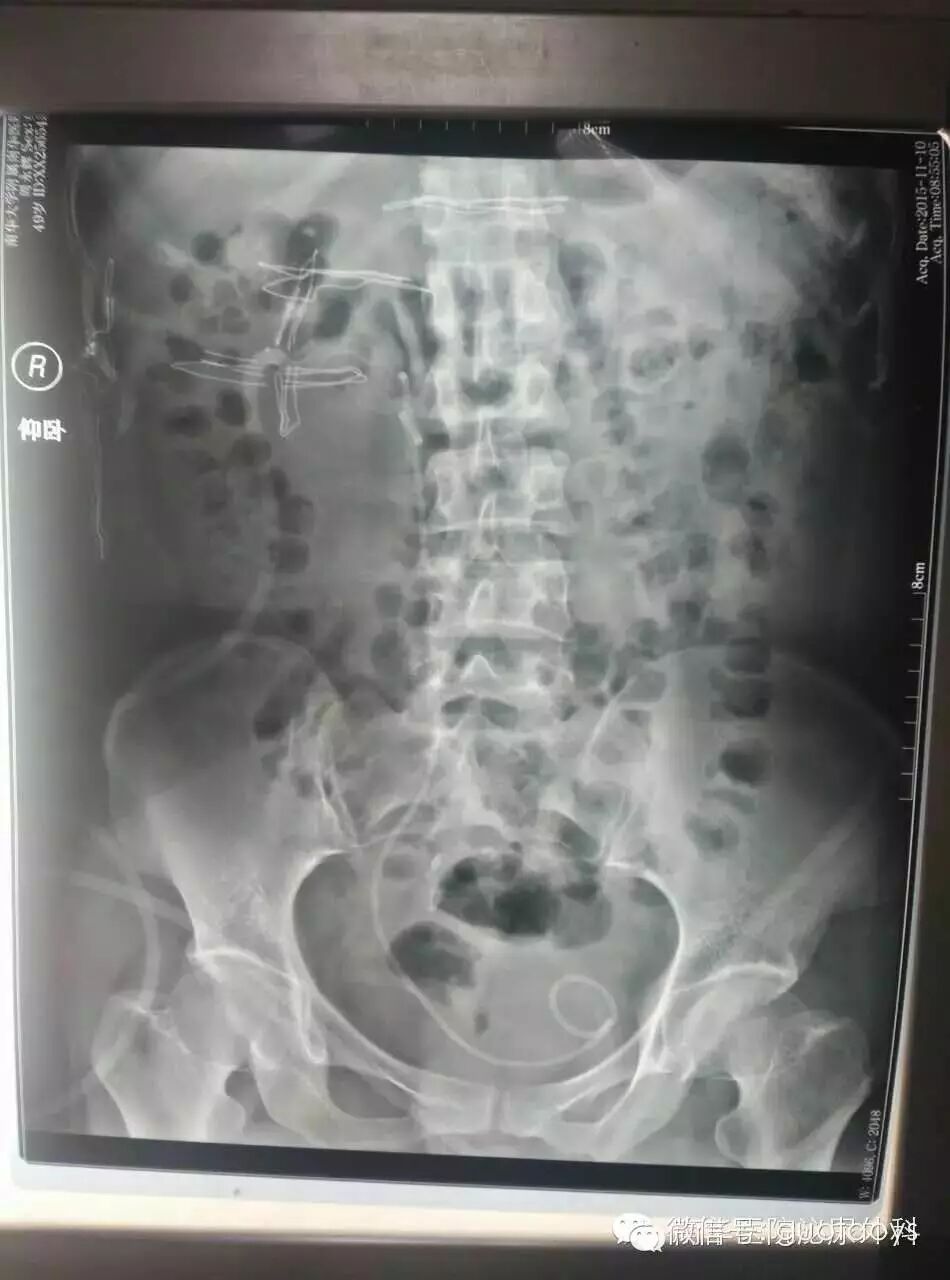

二期PCNL术后KUB。